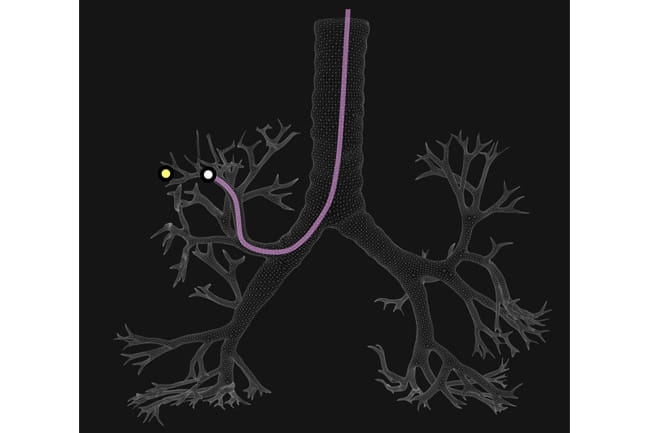

Illustration of a bronchoscope in a lung nodule

Nick Pastis, M.D., threads a bronchoscope into a patient’s lung. He will use a joystick to maneuver the bronchoscope to the exact position of a lung nodule.

This danger is being minimized at MUSC with a newly purchased robotic bronchoscopy machine that is the only one of its kind in South Carolina. This machine provides greater control to the physician and a less invasive procedure for the patient. It also allows the physician to navigate to far peripheral nodules that were previously unreachable and obtain adequate sample tissue.

“The robotic scope gets you there and lets you have very fine motor control of the tip of the scope way out in the lung,” Pastis says. “It has a mother-daughter scope configuration. The larger scope locks you in position, then you put out a very thin scope that allows you to steer through multiple branches of the lung and angle the needle directly into the nodule.”